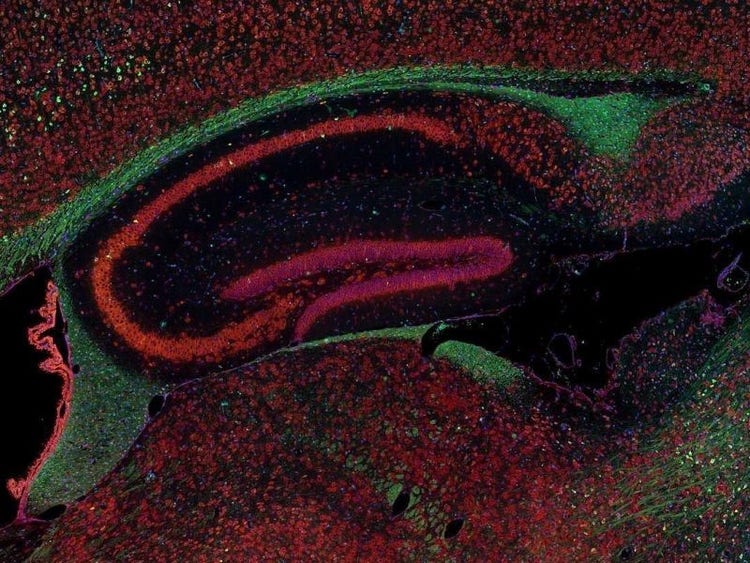

Fluorescence imaging of a mouse brain

これらの画像は一つひとつが独立した拡大画像に見えますが、すべて合わせると、蛍光イメージングで撮影されたマウスの脳の画像が形作られます。

イギリスの科学者、George G. Stokes卿は、蛍石に紫外線を当てると蛍光を発することを最初に発見し、「蛍光」という用語を作りました。Stokes卿は、蛍光は励起光よりも波長が長いことに気づき、今日では、この現象はストークスシフトとして知られています。蛍光顕微鏡法は、自然のまま(一次蛍光または自家蛍光と呼ばれます)か、蛍光を発することのできる化学物質で処理した場合(二次蛍光として知られています)かのいずれかで蛍光を発することのできる物質を研究するための優れた方法です。